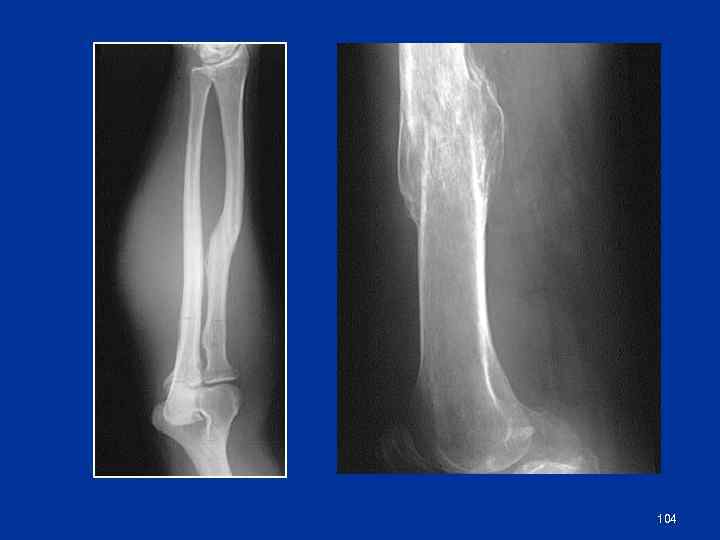

Патологическое заживление переломов Неправильно сросшиеся переломы Посттравматические синостозы Избыточная костная мозоль Асептический некроз (в т. ч. болезнь Кюммеляпосттравматический некроз тела позвонка) Несросшийся перелом Ложный сустав Неоартроз 103

104